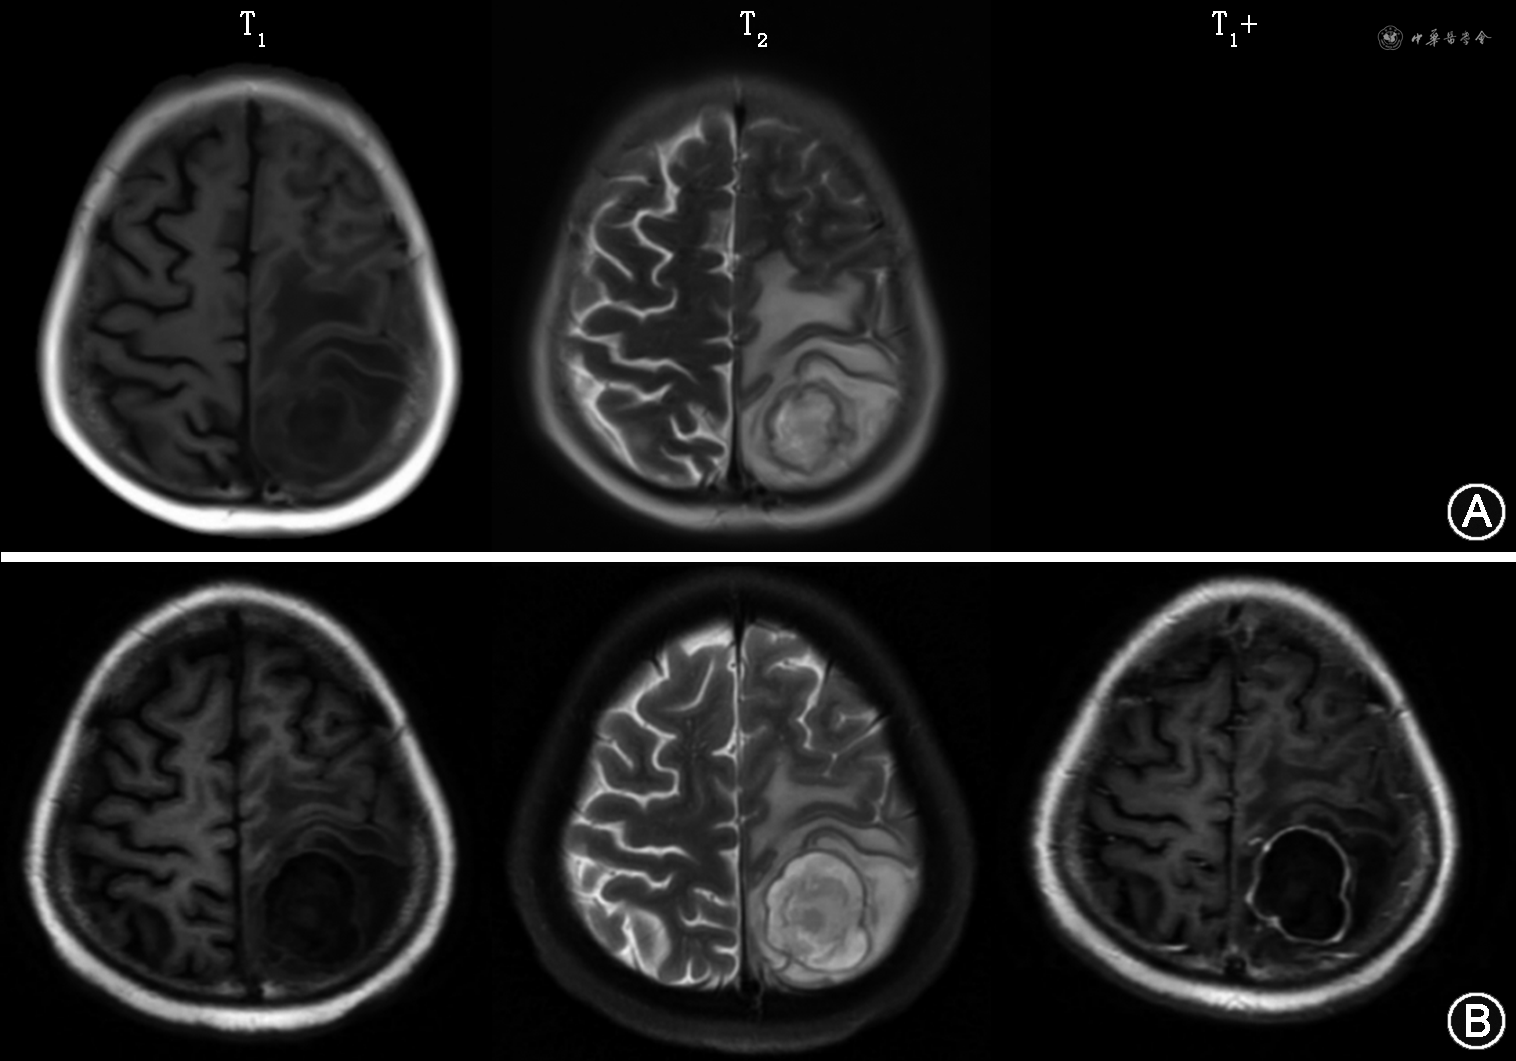

出院后患者未有抽搐发作,2021年12月复查头颅MRI示:左侧额叶靶形T1低信号、T2高信号,增强后环形强化,周围多发大片状T1低信号、T2高信号(图1B)。考虑颅内病灶为脓肿可能,再次收入病房,完善原发病评估:血常规、血肌酐无明显异常,血清白蛋白23 g/L,24 h尿蛋白4.49 g;抗SSA、抗Ro52抗体阳性,IgG 5.87 g/L,C3、C4正常。血清(1,3)-β-D葡聚糖试验(G试验)、半乳甘露聚糖试验(GM试验)均阴性。腰椎穿刺脑脊液压力为175 mmH2O,脑脊液常规、生化、细胞学、细菌、真菌涂片培养及脑脊液第二代测序(next-generation sequencing,NGS)均为阴性。PET/CT:左额叶白质区囊性结节,仅囊壁有轻度代谢活性,最大标准摄取值7.7,伴周围大片水肿。治疗上继续予泼尼松、羟氯喹、左乙拉西坦,加以罗氏芬2 g 1次/12 h静脉点滴17 d,复查头颅增强MRI未见变化(图1C)。多学科会诊建议开颅行手术切除活组织检查(活检),术前抗感染改为美罗培南2 g 1次/8 h+万古霉素1 g 1次/12 h。2022年1月25日全身麻醉后行神经导航下左额叶脓肿切除术,组织培养提示烟曲霉菌(图2,3),NGS回报烟曲霉菌、细环病毒、人类疱疹病毒5型,病理检查(图4)示:坏死物、真菌(曲菌)菌丝及肉芽组织,周边极少许水肿的神经组织。特染结果:过碘酸雪夫染色(periodic acid-Schiff staining)阳性,六胺银染色阳性。抗感染方案遂改为伏立康唑0.2 g 1次/12 h联合美罗培南2 g 1次/8 h。患者未再出现发热及神经系统症状,原发病好转后于2022年2月24日出院。出院后继续口服伏立康唑片0.2 g 1次/12 h,于2022年3月21日及2022年4月4日规律复诊,诉无癫痫再发,复查MRI示术后改变,术区类圆形信号影呈缩小趋势,边缘少许强化,未见环形强化(图1D、E)。患者已于2022年8月20停用伏立康唑。

例2 患者男性,20岁,主因皮疹、双下肢水肿9年余,间断发热、抽搐3个月余入院。2011年患者出现面部红斑,伴发热、乏力,抗核抗体、抗组蛋白抗体、抗核小体抗体、抗双链DNA抗体、抗SSA抗体、抗SSB抗体均阳性,大量蛋白尿、低补体血症,肾活检示狼疮性肾炎Ⅴ型,考虑“系统性红斑狼疮,狼疮性肾炎”,予甲泼尼龙冲击,序贯泼尼松35 mg 1次/d、霉酚酸酯1 g 1次/d,激素规律减量,治疗约2年。此后病情数次波动,予足量激素联合免疫抑制剂治疗有效。2021年3月21日患者出现高热,最高体温39.4 ℃,右侧上下肢抖动,发展至全身抽搐、牙关紧闭、意识丧失,持续约30 min后自行缓解,急诊予甲泼尼龙40 mg×5 d及对症处理后好转。2021年6月9日患者再次出现发热、头痛、抽搐,体格检查发现库欣面容,颈软,无抵抗,双下肢膝腱反射活跃,病理征阳性。头颅MRI提示左侧顶枕叶占位,环形强化,伴周围大片水肿带(图5A)。考虑SLE诊断明确,合并颅内感染可能,收入北京协和医院肾内科病房。完善原发病相关评估:血常规无明显异常,血清白蛋白25 g/L,血肌酐212 μmol/L,24 h尿蛋白5.01 g,红细胞沉降率103 mm/h,超敏C反应蛋白11.38 mg/L,抗核抗体滴度1∶80,斑点型,IgG 4.82 g/L。查血清G、GM试验均阴性。腰椎穿刺脑脊液压力235 mmH2O,脑脊液蛋白0.46 g/L,脑脊液白细胞计数10×106/L,脑脊液单核细胞计数2×106/L,培养、涂片均阴性,脑脊液NGS报日本马拉色菌及溶血葡萄球菌,考虑污染可能。在治疗方面,对原发病予暂停免疫抑制剂,泼尼松减量,颅内病灶予美罗培南2 g 1次/12 h×14 d经验性抗感染、降颅压、抗癫痫治疗,复查颅内增强MRI示占位较前增大,环形强化明显(图5B)。为明确颅内感染病原,患者于2021年7月12日行神经导航下脑脓肿外引流术,缓慢抽取脓液约7 ml送检,脓液NGS回报烟曲霉菌,真菌涂片可见较多真菌丝,真菌培养发现烟曲霉菌。术后予以伏立康唑200 mg 1次/12 h治疗,监测患者体温逐渐恢复正常,原发病控制稳定后出院。出院后继续口服伏立康唑200 mg 1次/12 h,2021年10月22日线上复诊,外院复查核磁示病灶明显缩小,目前继续伏立康唑治疗中。

T1+:对比度增强T1加权成像